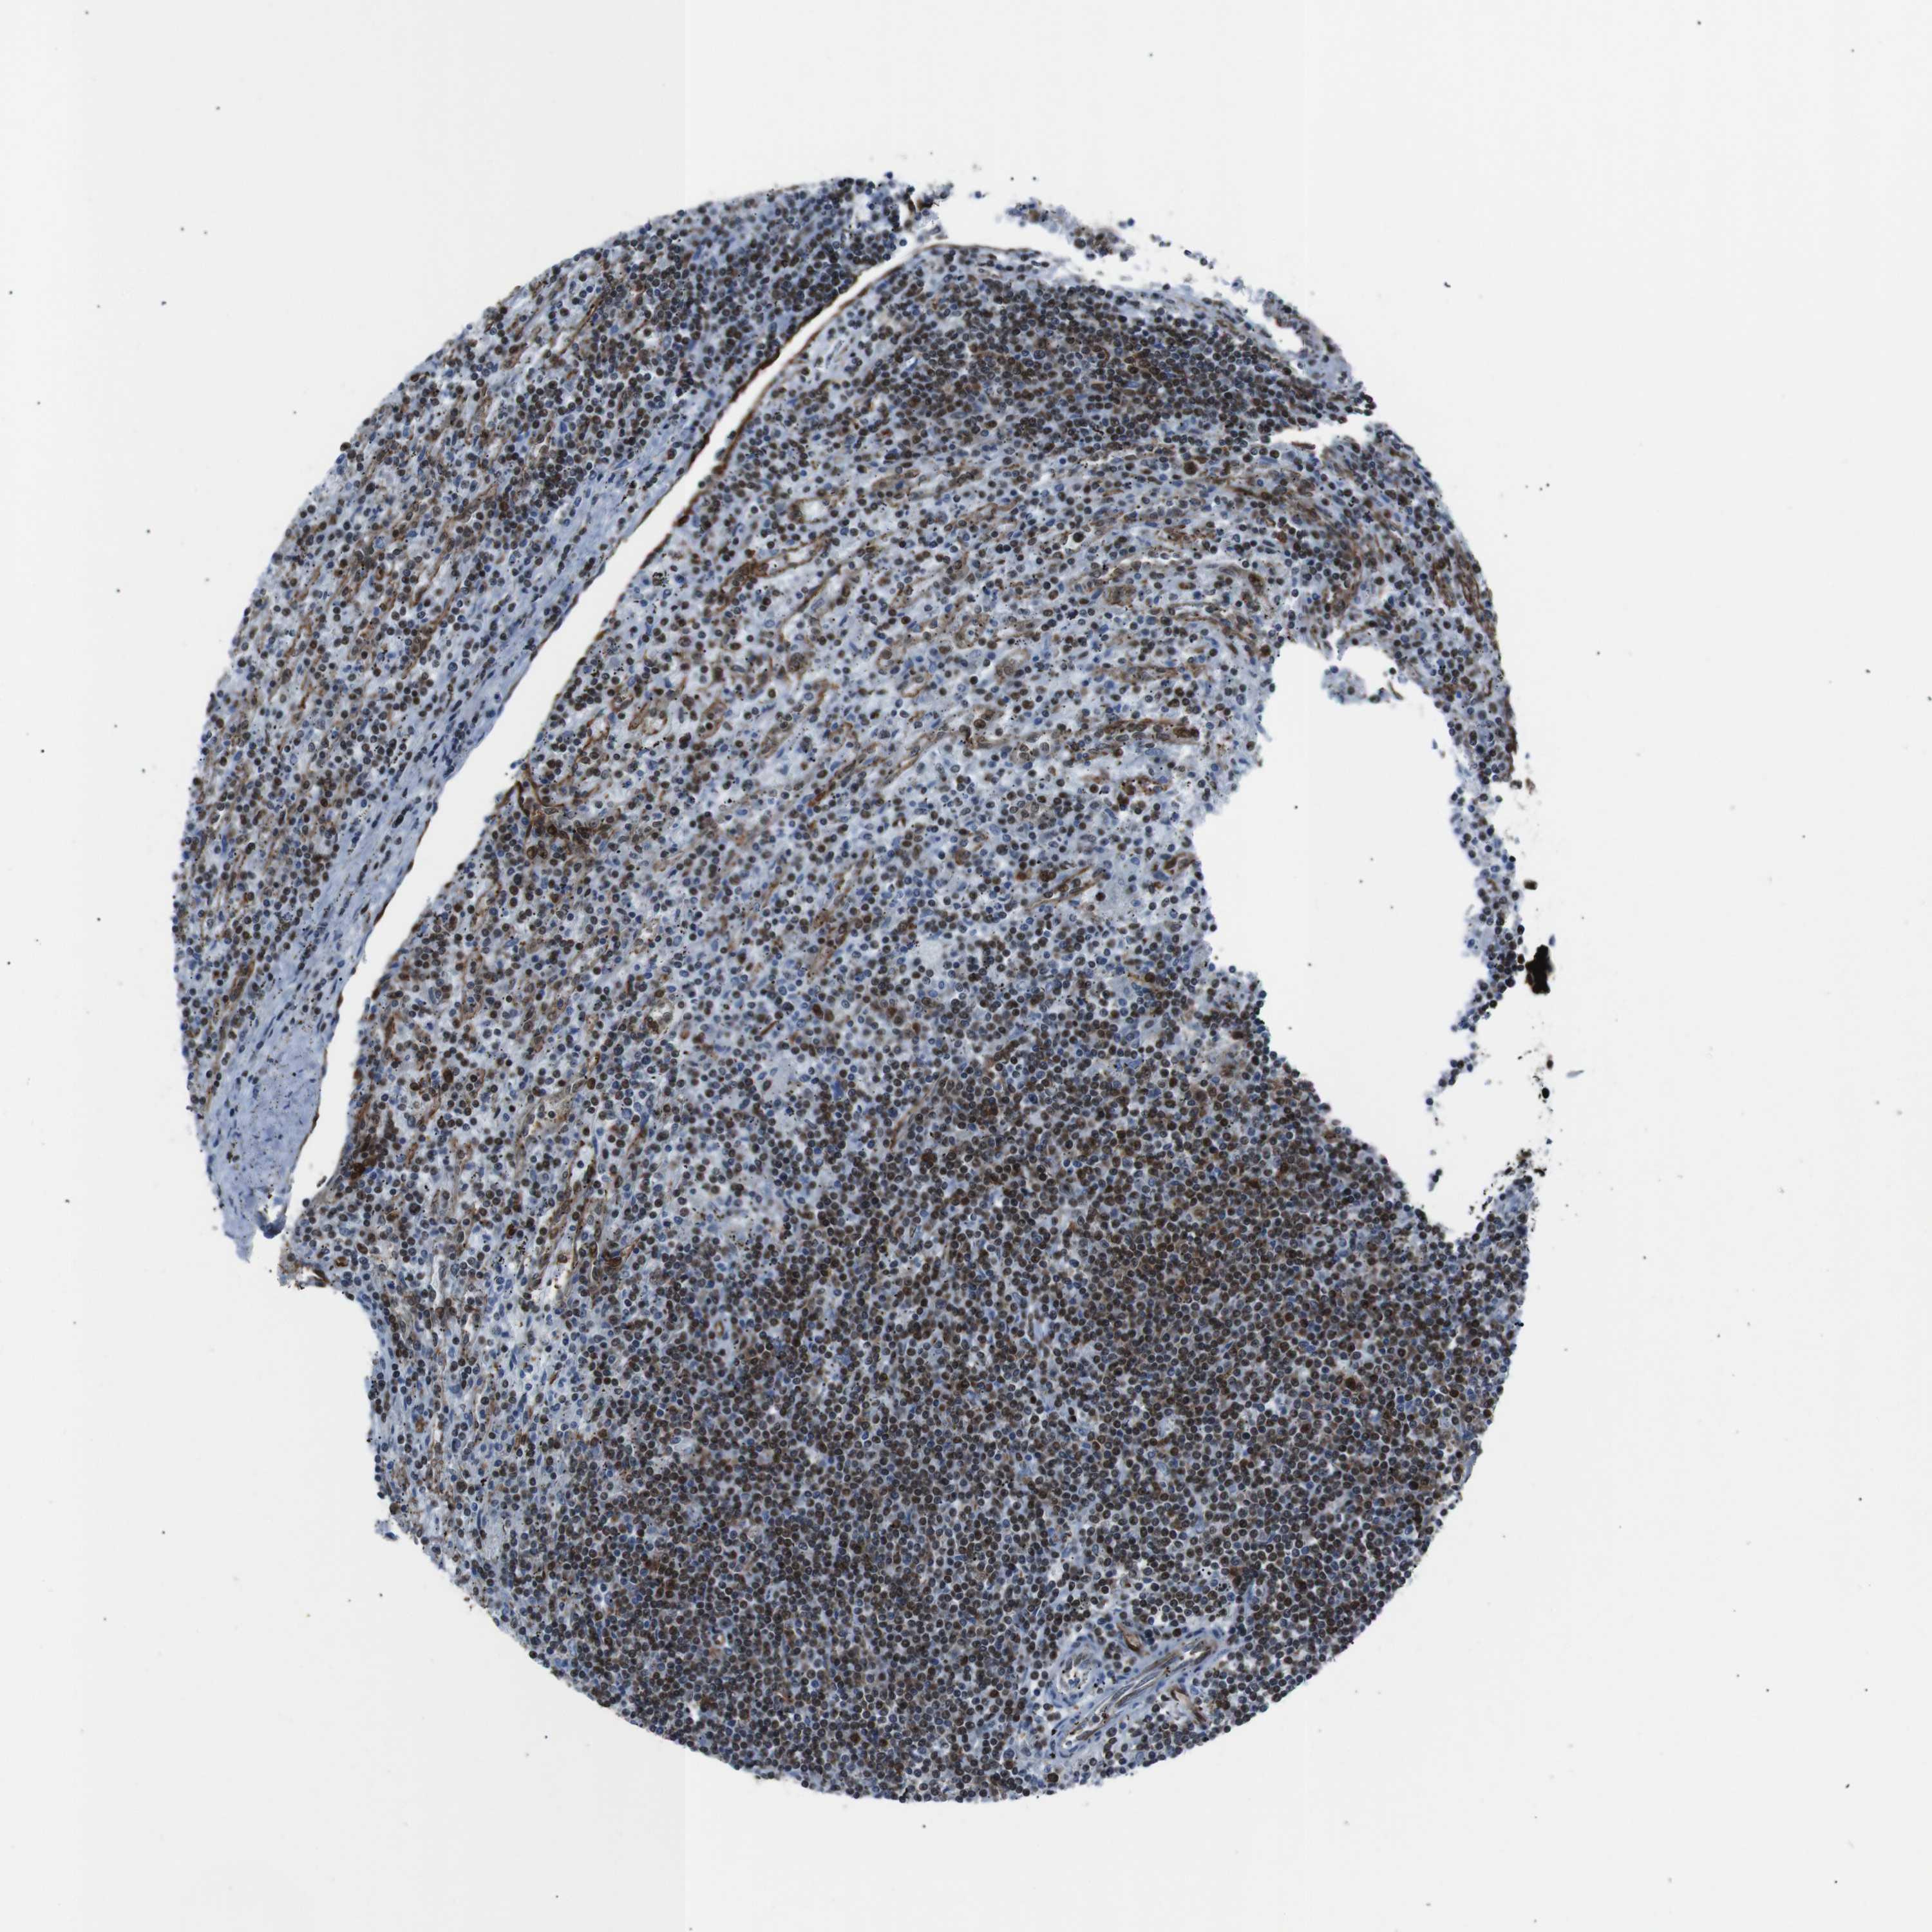

LYMPHOMA - Protein expressioni

A mouse-over function shows sample information and annotation data. Click on an image to view it in a full screen mode. Samples can be filtered based on level of antibody staining by selecting one or several of the following categories: high, medium, low and not detected. The assay and annotation is described here.

Each image is clickable and will lead to virtual microscopy that enables deeper exploration of all samples and also displays staining intensity scores, fraction scores and subcellular localization as well as patient and tissue information for each sample.

Antibody HPA041057

Staining

High

Intensity

Strong

Quantity

>75%

Location

Nuclear

Malignant lymphoma, non-Hodgkin's type, Low grade

Malignant lymphoma, non-Hodgkin's type, High grade